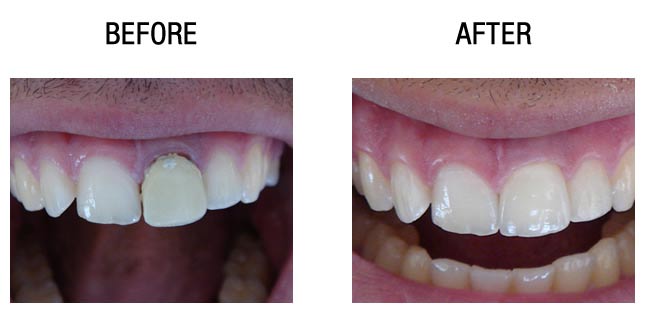

5、种植牙属于固定修复,假牙部分体积小、金属部分不外露、美观协调,不需要使用活动假牙必需的基托与卡环,没有异物感,使用起来非常舒适、方便。